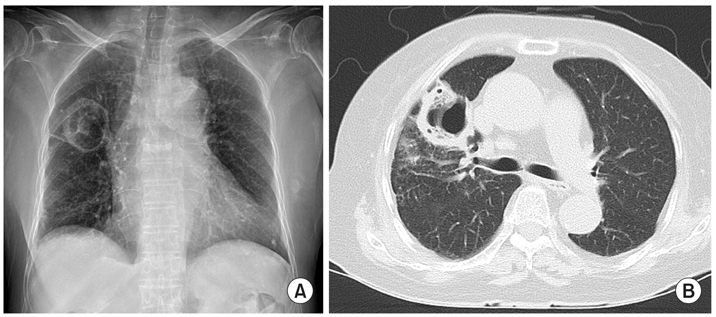

A 75-year-old female presented to the pulmonary department complaining of febrile sensation, cough and sputum for 2 weeks. She had a 15-year history of hypertension, diabetes mellitus, and osteoarthritis, and a 3-year history of adrenal insufficiency due to long-term intake of herb medication. She was taking 2.5 mg of prednisolone per day. Her heart rate was 90 beats per minute, respiration rate was 20 breaths per minute, and body temperature was 37.8℃. Auscultation of the chest revealed no abnormal lung and heart sounds. Laboratory findings revealed a white blood cell count of 12,440/µL (neutrophil 76.4%), C-reactive protein 56 mg/L, and glycated hemoglobin 7.5%. Chest X-ray revealed a cavitary lesion at right upper lobe. Chest CT scan showed a 4 cm-sized irregularwalled cavity with surrounding alveolar consolidation (

Fig. 1Chest imaging at presentation. (A) Chest X-ray shows a 4 cm-sized cavitary lesion at right upper lobe. (B) Chest computed tomography scan reveals a thick, irregular-walled cavity at right upper lobe.